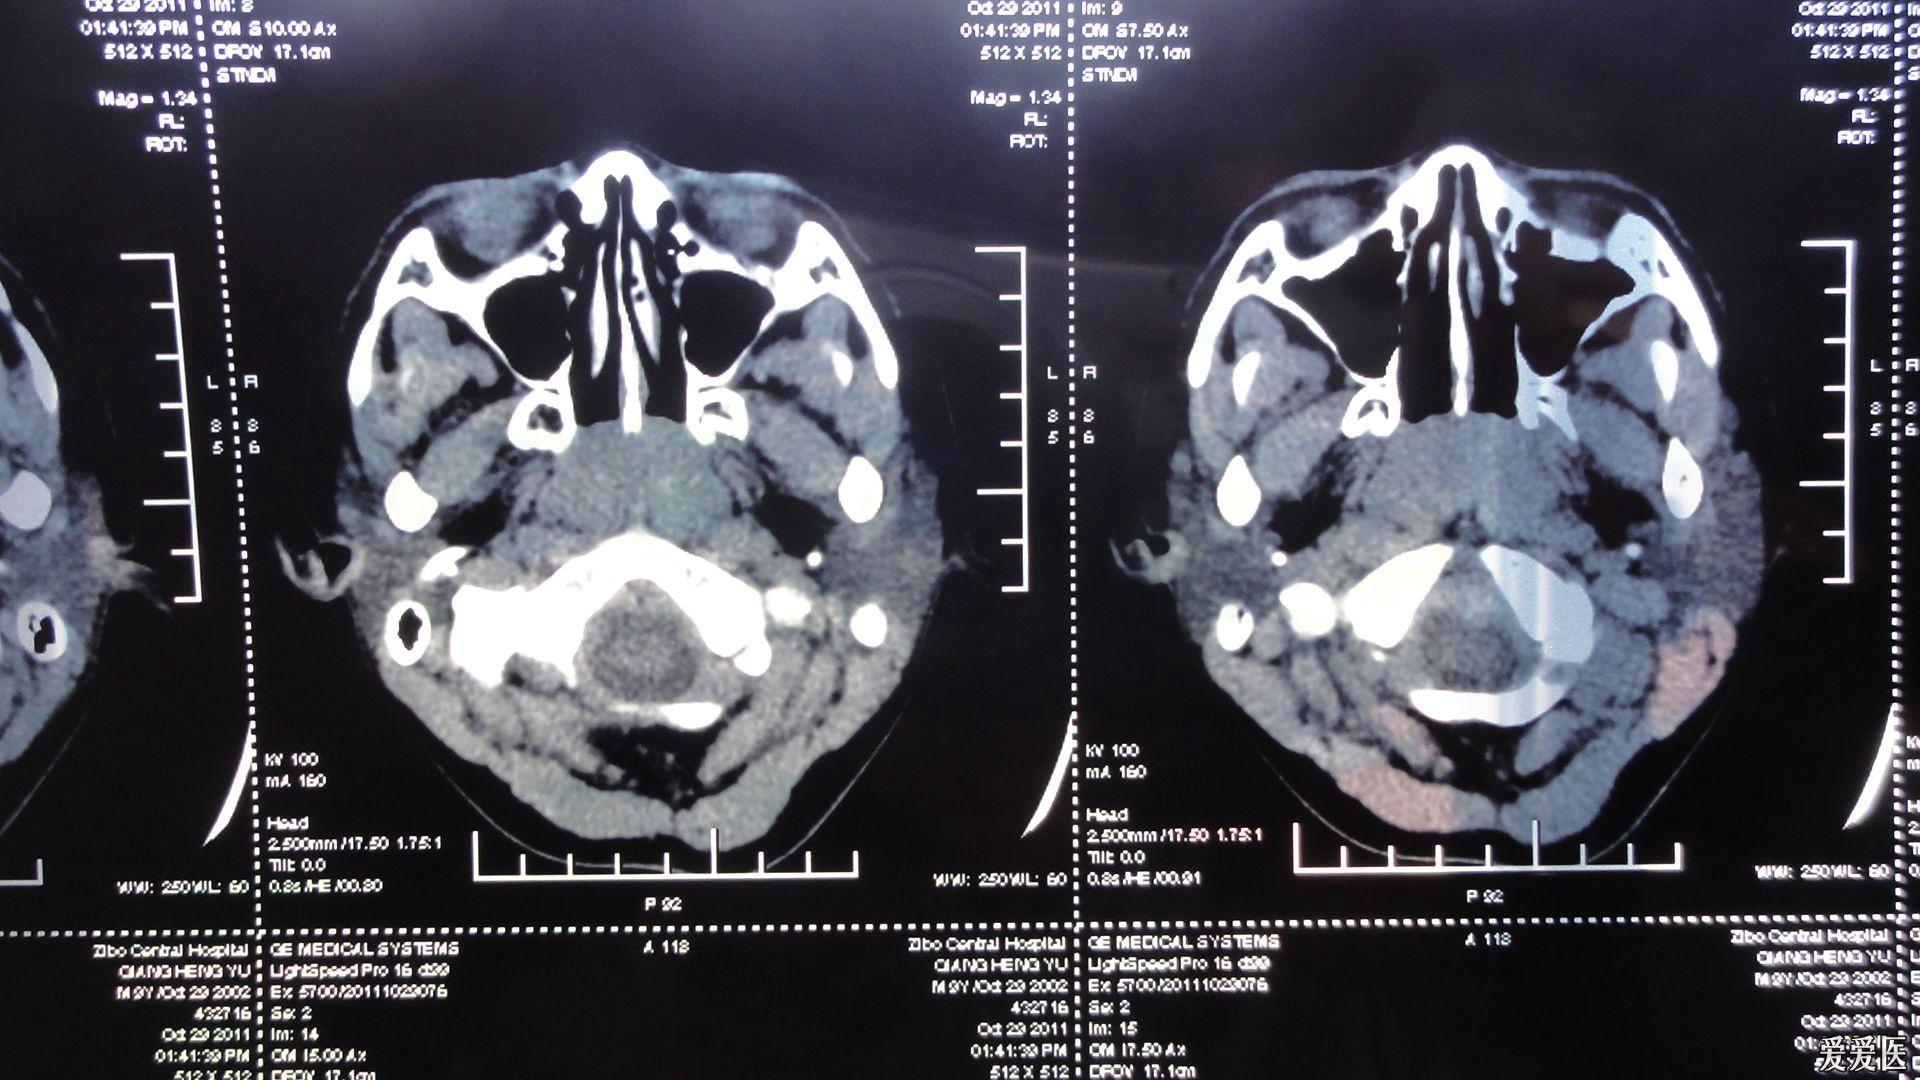

内科大夫求助增殖体肥大